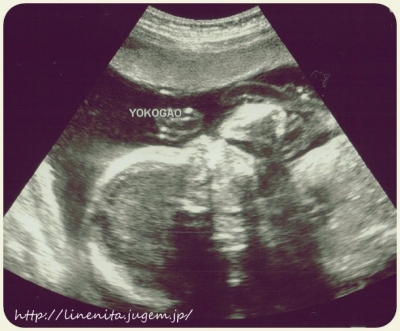

JUGEMテーマ:妊娠中のできごと 23週目の エコー写真。 手を口元に 持っていくところです。 (左が頭で少し鼻の 凹凸ができてます) この日は 病院に向かう時から スタンバイオッケーだよ!! と伝わってくるほど グルングルン お腹の中で動いていました。 今日は どんなエコーかな、と 楽しみにしていると 指しゃぶりの真っ最中でした。 「お、かわいいねぇ」と 先生が写真を撮ろうとした瞬間 クルリと姿勢を変えてしまい 写真は撮れませんでした。 それでも 手を顔に近づけたり 足を顔の辺り...